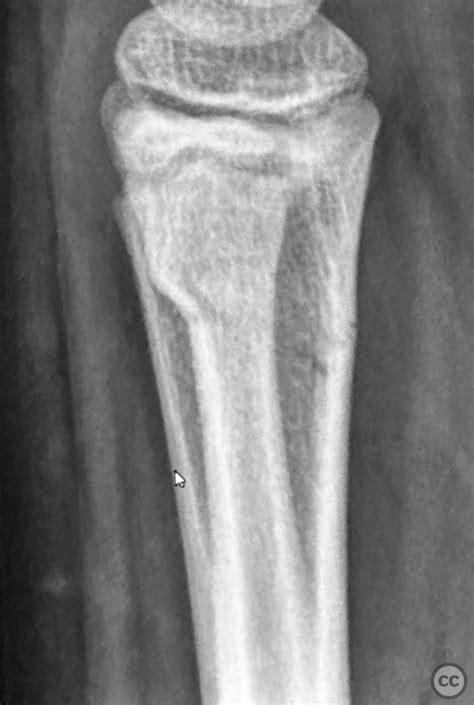

Misdiagnosed greenstick fracture of the distal radius: Lost reduction and surgical intervention

The pediatric skeleton is unique because of the presence of growth plates and a thicker, more resilient periosteum—the fibrous sheath covering the bone. When a child falls, the energy absorbed by the forearm is often enough to cause a localized compression of the bone cortex without snapping it in two. This results in the characteristic "bulge" or "buckle" deformity seen in a buckle fracture radius.

Because the bone is not fully broken through, these injuries are generally stable. The surrounding periosteum remains intact, acting like a natural splint. However, even though they are considered "minor" fractures, they are still painful and require clinical attention to differentiate them from more severe angulated fractures or greenstick fractures, where one side of the bone bends and the other side actually breaks.

Radiologists look for a small "kink" or cortical disruption on the distal radius. Sometimes, a subtle thickening of the cortex is the only diagnostic clue. If the initial X-ray is inconclusive but the clinical suspicion remains high, doctors may recommend a follow-up visit or immobilization as a precautionary measure.